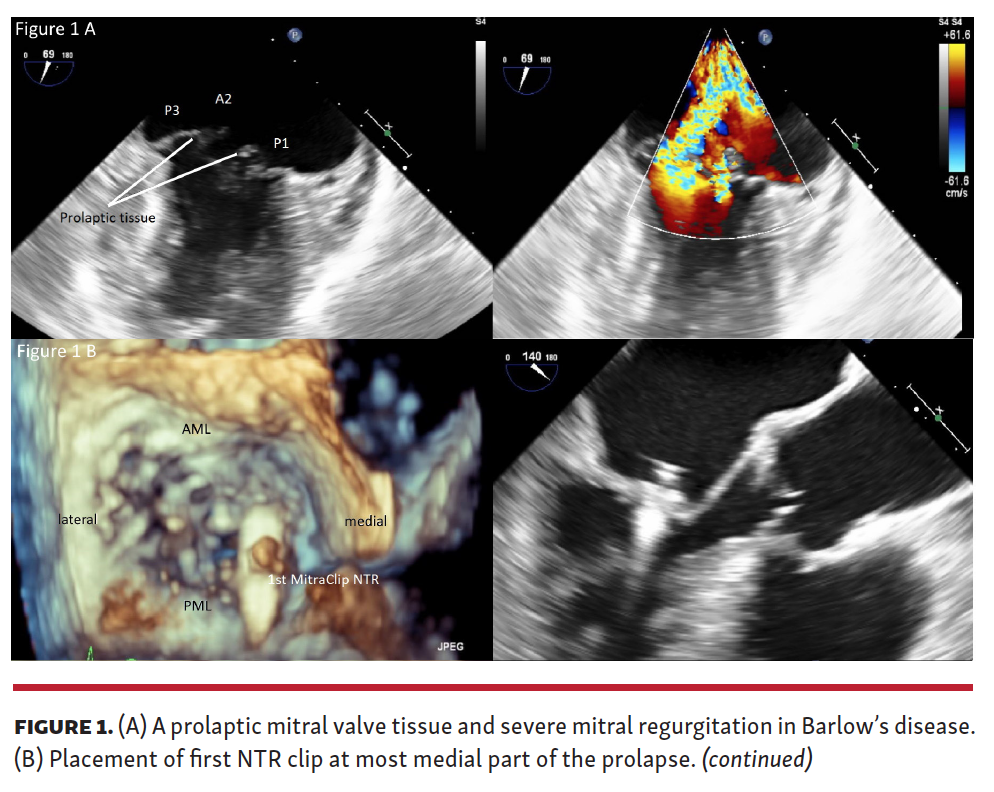

In patients with Barlow’s disease, mitral valve pathology is multidimensional. Barlow’s disease is characterized by extensive mitral valve myxoid degeneration, chordae elongation, and mitral valve annular dilation leading to prolapse. Therefore, any strategy of percutaneous repair should consider increased mitral valve tissue frailty. Percutaneous mitral valve repair with MitraClip XTR (Abbott Vascular) has been proposed in patients with Barlow’s disease, as the extended length of the MitraClip XTR may facilitate “grasping” and limit the number of clips. However, the design of the MitraClip XTR includes arms that are 3 mm longer than those on the NTR device as well as 2 additional frictional elements, and requires patient selection based mainly on mitral valve tissue quality. We summarize our rationale for using the shorter and smaller MitraClip NTR in patients with Barlow’s disease.

(1) Due to tissue abundance in patients with Barlow’s disease, no elongated MitraClip arms are needed to simultaneously grasp both leaflets (Figure 1A).

(2) We start from the most medial part of the prolapse, close to the commissural tissue (fibrotic component) (Figure 1B).